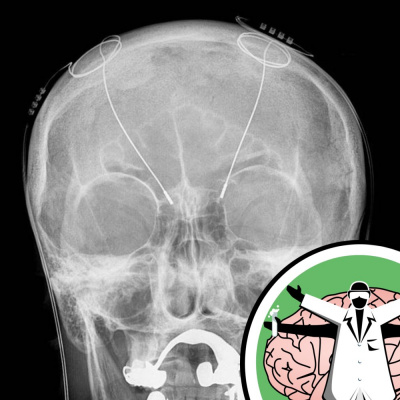

A Wired Society

Memory boosting drugs, the military, the legal system and enhancing athletes mental focus and muscle tone. Where should neuroscience stop? How a revolution in technology is bringing an unprecedented flood of information about the brain and with this, concerns over use. Like this podcast? Please help us by supporting the Naked Scientists